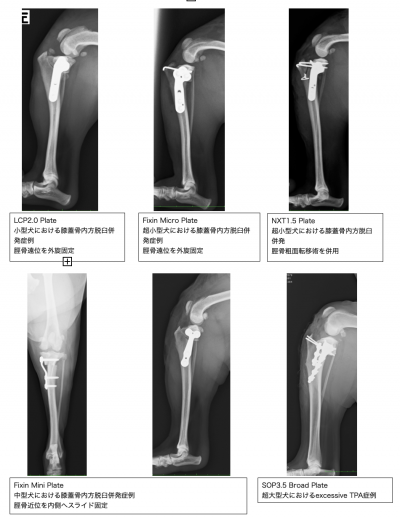

私自身、TPLO法を始めるまでは、糸を用いて固定する関節外制動法(Flo法)を行っていました。しかし、術後に糸が緩んだり切れたりすることで、再手術になることもしばしばありました。そして、Flo法の変法であるスーチャーアンカー法やタイトループ法なども含めて、100症例以上の手術を行いましたが、術後の成績は改善しませんでした。そういう経緯もあり、8年程前からTPLO法を用いるようになりました。現在では、私のTPLO法における執刀症例数は、160症例以上になっております。この160症例のうち、再手術が必要であった症例は、わずか1症例であり、術後3ヶ月の時点で跛行が改善しなかった症例は、0症例でした。この成績は驚異的だと思います。獣医整形外科において、これほど効果的で、安定した成績をもたらすことのできる術式は、他にないと思っています。現在では、インプラントメーカー各社から、多様な形状のTPLO用プレートが開発されているため、膝蓋骨内方脱臼を併発した症例や、超小型犬や猫であっても、良好な成績を得ることができています。よって、現在T P L O法における私の実績は、相模原町田地域においては、最上位にあると自負しております。

様々な形状のTPLOプレートを用いた当院での手術症例